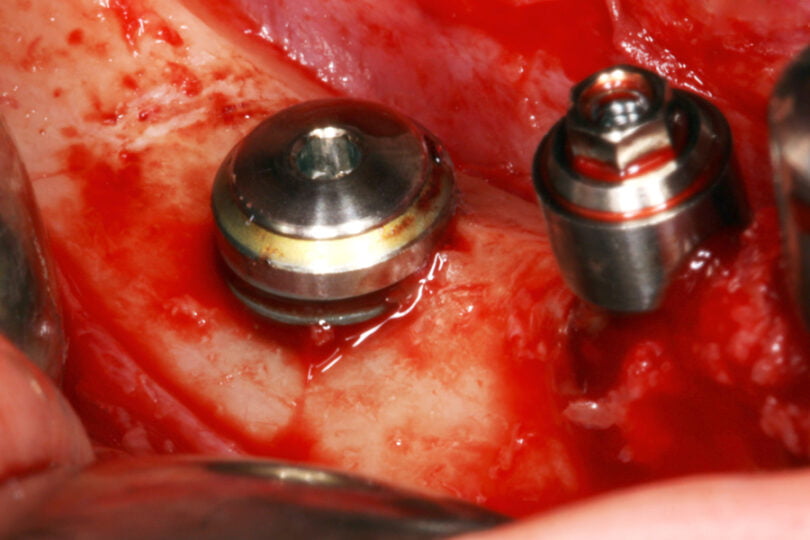

Em nenhum caso foram utilizadas técnicas cirúrgicas complementares na cirurgia de implantes e todos os implantes foram realizados em dois tempos cirúrgicos, com um tempo de espera de 3 meses até à carga.

As seguintes imagens apresentam um dos casos incluídos no estudo (figura 03 – 15).